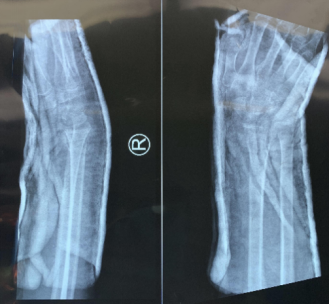

(裂纹型骨折) (移位型骨折) 实际上,“骨裂”究其本质上还是骨折,只不过骨折不移位或移位不明显罢了。换言之,骨裂是骨折的一种类型,而非与骨折相提并论,其治疗原则和其他类型骨折并无差异,都是复位、固定和功能锻炼。 其二,骨裂就是骨折,不固定或固定时间不够依然会出现移位或者骨折延迟愈合、不愈合,千万不能区别对待。说到这里,就不得不提及骨折的治疗原则——“复位、固定、功能锻炼”,虽然只有短短的7个字,却饱含了很多重要的信息。复位是骨折后首要解决的问题,这个复位根据骨折部位不同有的需要功能复位,有的需要解剖复位。总之,骨科医生治疗骨折的第一步就是复位,骨裂的患者这一步自然不用多做。 接下来要解决的问题就是固定,为什么要固定?“固定”解决的问题是复位后骨折断端的维持,所谓骨裂的患者往往骨折断端都没有明显移位,但是这并不代表骨折不会出现继发性移位,因为没有有效固定或者未按医嘱要求固定,导致不得不采取手术治疗的案例临床上也比比皆是,有的患者觉得只是骨裂就掉以轻心、麻痹大意,不遵医嘱佩戴石膏或支具,殊不知这些原则都是用血泪的教训总结出来的,目的就是同样的错误不可再犯,不要去承受这本可避免的痛。 (骨折后石膏固定) 有时候规避风险只需要一个合适的石膏,固定不牢,势必移位,移位之后再手术往往导致错过最佳的锻炼的时间,一来二去就是出现关节僵硬、骨质疏松、肌肉萎缩等这样那样的骨折并发症,而这一切也仅仅是一个石膏就可以避免的。 况且,没有骨折的患者,关节部位的韧带损伤常常也是需要石膏固定的,目的是通过“制动”促进韧带的修复。 总之,石膏固定的目的是在保护或者维持良好的复位,是加分项而非减分项,能用石膏固定解决的骨折说明骨折不算严重,预后还是很好的。 其三,“动静结合”的理念贯穿了骨折治疗的自始至终。石膏固定并非不能活动和锻炼,其固定的只是局部,没有石膏固定的其他部位可以动也鼓励多动,可以避免很多骨折并发症的发生。众所周知,石膏固定限制骨折局部的活动,非石膏固定的区域可自由活动,需注意“上肢不提物、下肢不负重”这一基本要求。 固定骨折局部的目的是为骨折愈合提供一个稳定的内环境,促使其早期纤维连接直至中后期形成内外骨痂实现骨折的愈合。在普通大众看来,带上石膏非常不方便不能洗澡;非常不好看被人嘲笑;非常不舒服不太透气。可是这些理由在我们看来是站不住脚的。 (移位后畸形手术治疗) 骨折本身就是一件麻烦的事情,如果仅仅是怕麻烦而不去石膏固定的话,那很可能会因为图省事而继发的骨折断端移位、延迟愈合、不愈合等并发症,届时增加的就是金钱和时间,而得到的结果是关节的僵硬和肌肉萎缩,细想起来极不划算,这不是人们常说的那句古话:捡个芝麻丢个西瓜,得不偿失啊! 骨折患者的幸福都是一样的而不幸却是各不相同的。在相对简单骨折的治疗中遵循原则、遵从医嘱相信科学、有效固定依然是行之有效的方法。